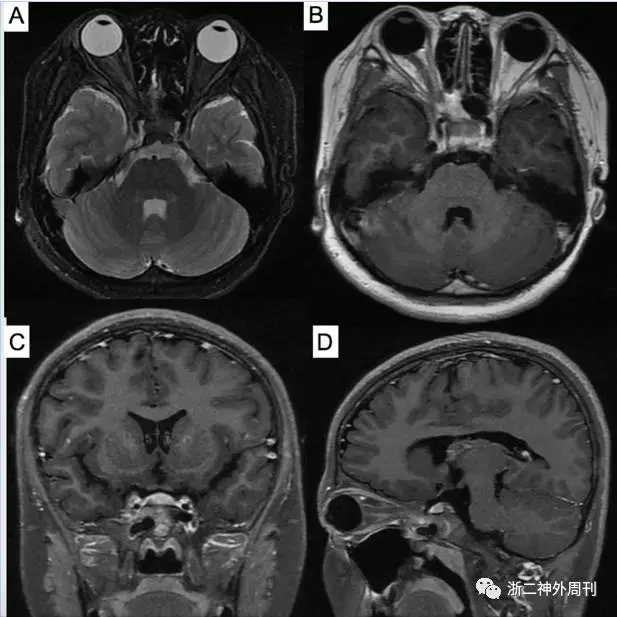

协和医院最终出院诊断为头痛原因不明,中小血管炎可能。予美卓乐4mg qd,后加用甲氨蝶呤 4片 qw口服治疗。1年后患者复查头颅MRI示右侧眶尖-海绵窦病变较前缩小缓解(图3)。目前仍在继续随访中。

图3. 术后1年复查头颅MRI:A)T2加权像轴位、B)增强后轴位、C)冠状位和D)矢状位示见右眼眶尖部-海绵窦病变较术前缩小缓解。